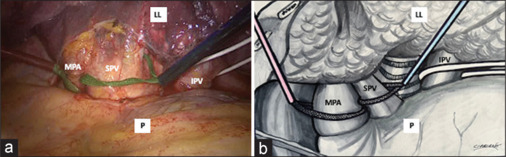

复杂的肺门解剖结构对胸外科医生来说可能是技术上的挑战,特别是在视频辅助胸外科肺叶切除术中。在这种情况下,为了防止出血并发症和转向开胸手术,提出了几种近端和远端血管控制方法。在此,我们提出了一种在具有挑战性的胸腔镜下左下叶切除术中对肺癌和叶间淋巴结病患者进行不必要的肺动脉阻塞和保留肺静脉的技术。

Complicated hilar anatomy may be technically challenging for thoracic surgeons, especially during video-assisted thoracic surgery lobectomy. In such instances, to prevent hemorrhagic complications and conversion to open thoracotomy, several methods of proximal and distal vascular control have been proposed. Here, we present a technique of unnecessary occlusion of the main pulmonary artery and preserved pulmonary vein during a challenging thoracoscopic left lower lobectomy in patient with lung cancer and interlobar lymphadenopathy.